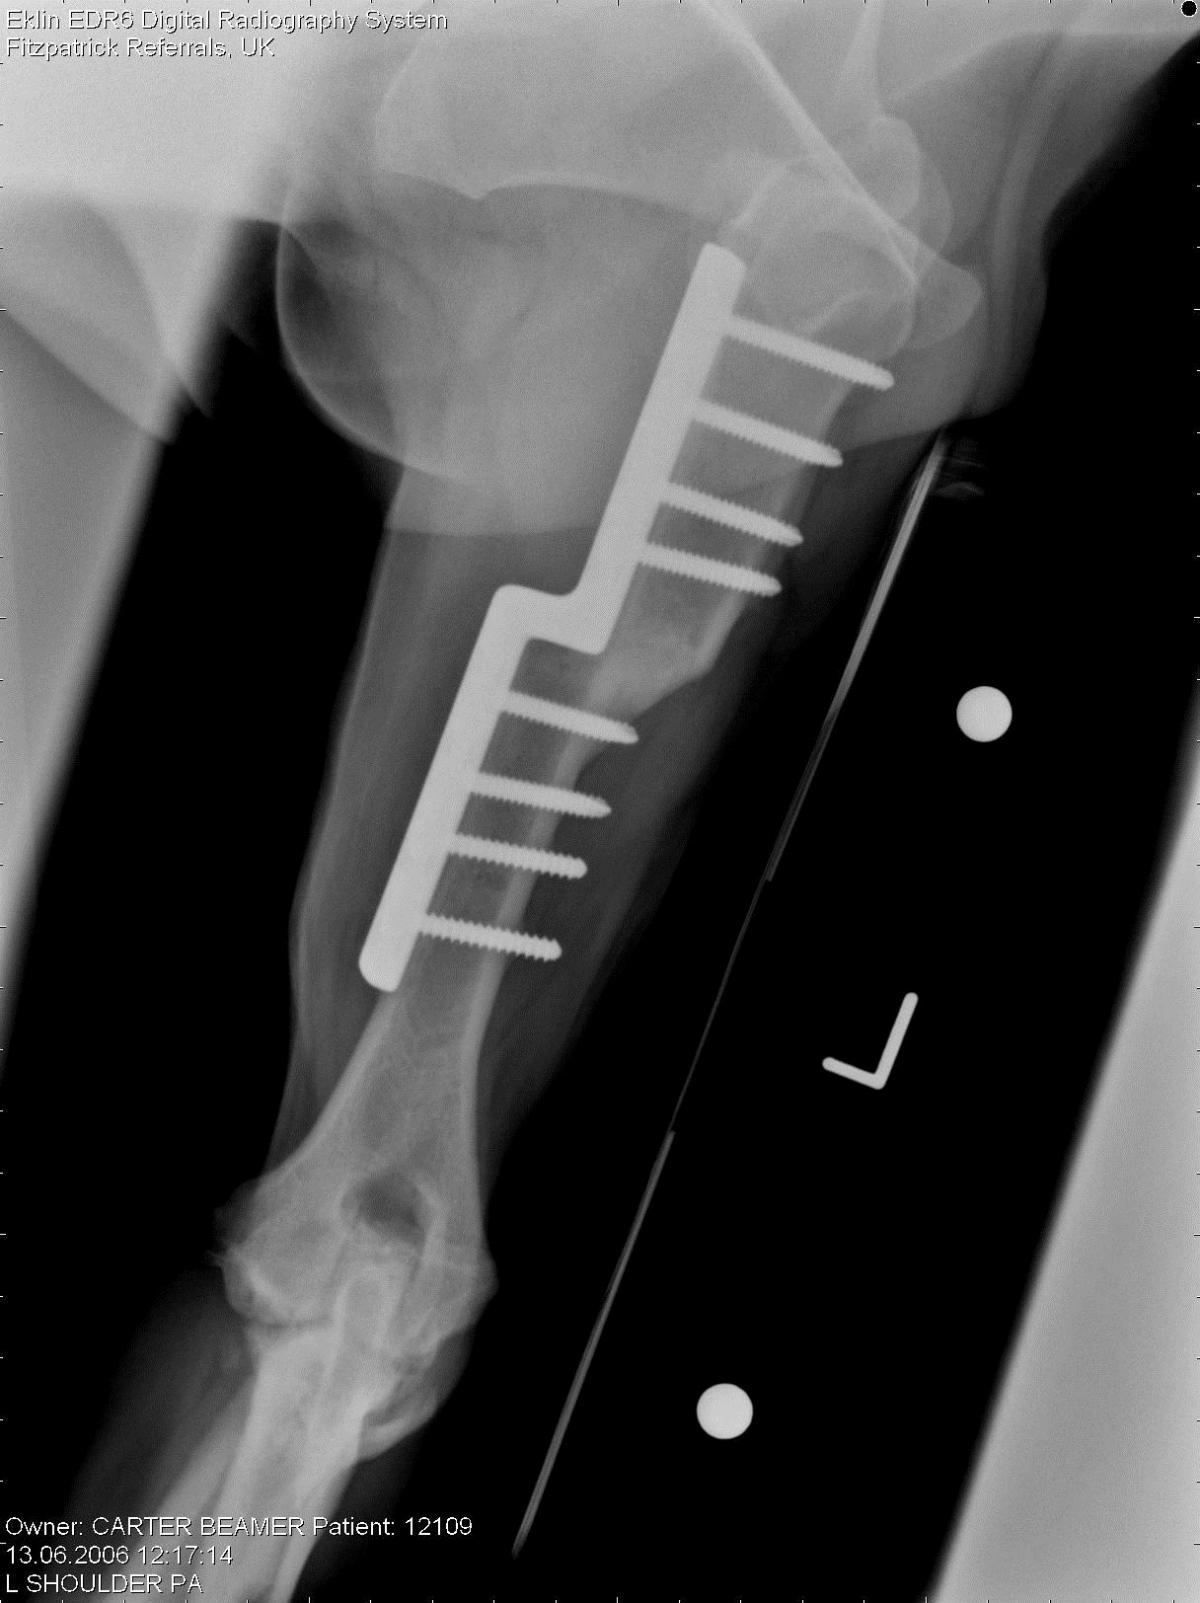

SHO sliding humeral osteotomy

nach sechs Wochen verheilte SHO (Noel Fitzpatrick)

Die SHO (sliding humeral osteotomy) ist eine relativ neue Operationstechnik zur Bekämpfung hochgradiger Lahmheiten in Folge einer Ellbogengelenksdysplasie. Trotz der Tatsache, dass zur Zeit nur eine handvoll Tierärzte für diese Operationstechnik lizensiert sind, nimmt die Zahl der operierten Tiere rasant zu, da in vielen Fällen dies die einzige Möglichkeit ist, Hunden mit Ellbogengelenksarthrose im Endstadium zu helfen.

Durch eine Korrektur des Oberarmes wird die Belastung des Ellbogengelenkes verändert. Die in vielen Fällen wenig betroffenen äußeren Anteile des Ellbogengelenkes werden mehr belastet, die inneren Anteile, hier ist der Knorpel sowohl an Oberarm als auch Unterarm verschwunden, entlastet. In Studien konnte nachgewiesen werden, dass durch diese Entlastung sich mit der Zeit sogar eine Art Ersatzknorpel über den vorher blanken Knochen legt. Die starken Veränderungen des inneren Anteiles des Ellbogengelenkes werden auch als mediales Compartment Syndrom bezeichnet. Diese Erkrankung war bis zur Entwicklung der SHO Technik nicht behandelbar.